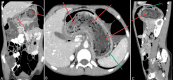

Figure 1

Figure 1. Computed tomography images - coronal (A), axial (B) and sagittal (C) views of abdomen showing stomach bezoar (red arrows) extending through entire stomach (green arrows).